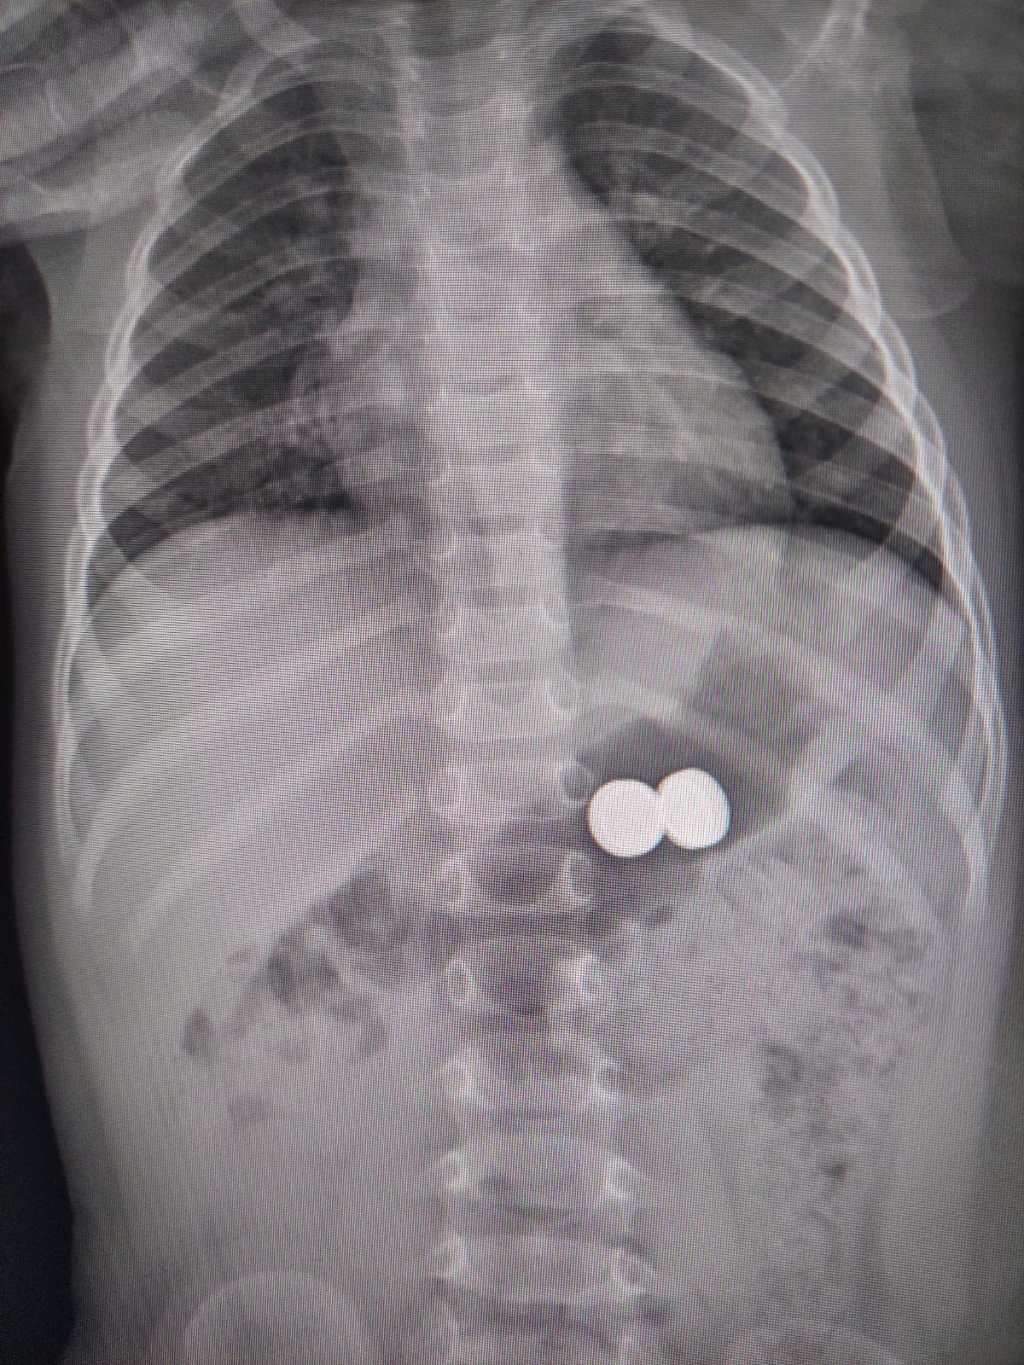

Una bambina di un anno è stata condotta d’urgenza all’ospedale Garibaldi-Nesima, dopo aver ingerito due batterie a bottone. Il pronto intervento dei medici ha permesso di rimuovere i corpi estranei senza conseguenze gravi.

Una volta arrivata al Pronto Soccorso Pediatrico, è stato prontamente allertato il gastroenterologo, dott. Domenico Catarella, insieme agli anestesisti della sala operatoria, dott. Giuseppe Calabrese e dott.ssa Lucia Terranova. Grazie alla loro tempestiva collaborazione, si è proceduto con successo alla sedazione e rimozione dei corpi estranei.